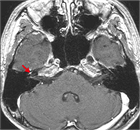

著者: 村上信五 名古屋市立大学付属東部医療センター 耳鼻咽喉科

監修: 小島博己 東京慈恵会医科大学 耳鼻咽喉科

1. 日本顔面神経学会:顔面神経麻痺診療ガイドライン 2023年版 第2版